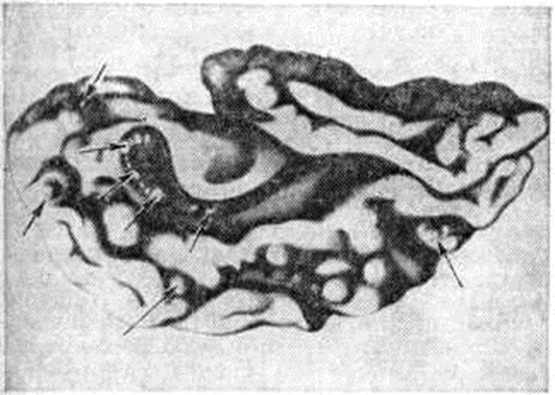

Туберозный склерозТуберозный склероз (sclerosis tuberosa; латынь tuberosus бугристый; склероз; синонимы: болезнь Бурневилля, болезнь Бурневилля — Прингла) — наследственное прогрессирующее заболевание из группы факоматозов, характеризующееся сочетанным поражением нервной системы, кожи, глаз, костной и эндокринной систем, внутренних органов. Впервые описан в 1863 год Ф. Реклингхаузеком. В 1880 год Бурневилль (D.-M. Bourneville), выделив это заболевание в отдельную нозологическую форму, ввёл термин туберозный склероз и детально описал ранние неврологический симптомы, изменения кожи и другие В 1890 год Прингл (J. J. Pringle) подробно изучил аденомы сальных желёз кожи лица и подчеркнул, что они характерны для Туберозный склероз По данным Пенроуза (L. S. Penrose), Туберозный склероз в общей популяции встречается с частотой примерно 1:600 000, среди больных с различной степенью умственной отсталости — 1:30 000. Этиология. В развитии Туберозный склероз большую роль отводят генетическим факторам. Семейные формы заболевания нередко наблюдаются в нескольких поколениях. Наследуется Туберозный склероз по аутосомно-доминантному типу с неполной пенетрантностью мутантного гена (смотри полный свод знаний: Пенетрантность гена). Близнецовый метод (смотри полный свод знаний) исследования обнаруживает высокую конкордантность по признакам болезни у монозиготных близнецов. Патогенез. Предполагается, что в основе заболевания лежит генетически обусловленное нарушение развития зародышевых клеток, приводящее к эктомезодермальным дисплазиям с образованием склонных к неопластической трансформации опухолевидных узлов в центральная нервная система и внутренних органах. Патологическая анатомия. Головной мозг при Туберозный склероз обычно увеличен по сравнению с возрастной нормой, однако иногда наблюдают и микроцефалию (смотри полный свод знаний). Кора головного мозга на отдельных различной величины участках белесовато-желтоватого цвета и большей, по сравнению с окружающей тканью, плотности. В центре участков изменённой коры имеются неглубокие западения, в которые погружаются сосуды. На разрезах полушарий головного мозга в коре обнаруживается различное количество грибовидных опухолеподобных образований, или бугров (рисунок 1); выявление их легло в основу названия заболевания. Единичные или множественные сероватые бугорки размером от булавочной головки до нескольких сантиметров в диаметре также обнаруживают в белом веществе полушарий головного мозга, в боковых желудочках, чаще вблизи ленты таламуса, реже в передних и нижних рогах боковых желудочков, в сильвиевом водопроводе (водопровод среднего мозга) и в четвёртом желудочке. В некоторых случаях Туберозный склероз изменения имеются и в мозжечке. Опухолеподобные образования могут нарушать отток цереброспинальной жидкости из желудочков и приводить к развитию внутренней гидроцефалии (смотри полный свод знаний). Эти образования обычно обызвествлёны, причём очаги обызвествления расположены чаще в глубине бугра. При гистологический исследовании туберозных участков в коре головного мозга обнаруживают атипичные, причудливой формы крупные нейроны (рисунок 2), аксоны которых нередко направляются к поверхности коры, сплетаются в клубки, внедряются в стенки сосудов. В коре обнаруживают и крупные атипичные клетки с одним-двумя пузырьковидными ядрами, цитоплазма которых при окрашивании тионином приобретает бледно-голубую окраску. Эти клетки, как установлено современными иммунологический исследованиями, также являются нейронами, а не астроцитами, как предполагалось ранее. В коре головного мозга имеются и нарушения нормальной цитоархитектоники с отсутствием нейронов, их атрофией и вакуолизацией. Кора головного мозга нечётко отграничена от белого вещества, в ней определяются выраженный глиоз (смотри полный свод знаний), аргентофильные образования, зернистые шары, расположенные по ходу сосудов (появление зернистых шаров некоторые исследователи связывают с деструктивными процессами, обусловленными частыми эпилептическими припадками). Стенки сосудов мозга утолщены, отмечаются признаки фиброза и гиалиноза (смотри полный свод знаний). Мягкая и паутинная оболочки головного мозга утолщены, в последней увеличено количество меланофоров. |

Рис. 2. | ||